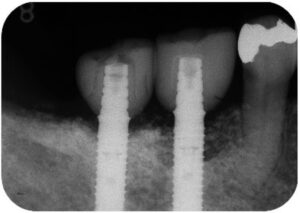

他院で下顎の第1、第2大臼歯の抜歯後にインプラント治療された患者様が、インプラント周囲粘膜の痛みと排膿を主訴に来院されました。

レントゲン写真を撮影すると、インプラント周囲の骨に影が認められ、インプラント周囲炎が強く疑われました。

骨吸収の大きさからインプラントの除去も選択肢の一つでしたが、患者様の強い希望により、十分な説明と同意のもと再生治療を行いました。